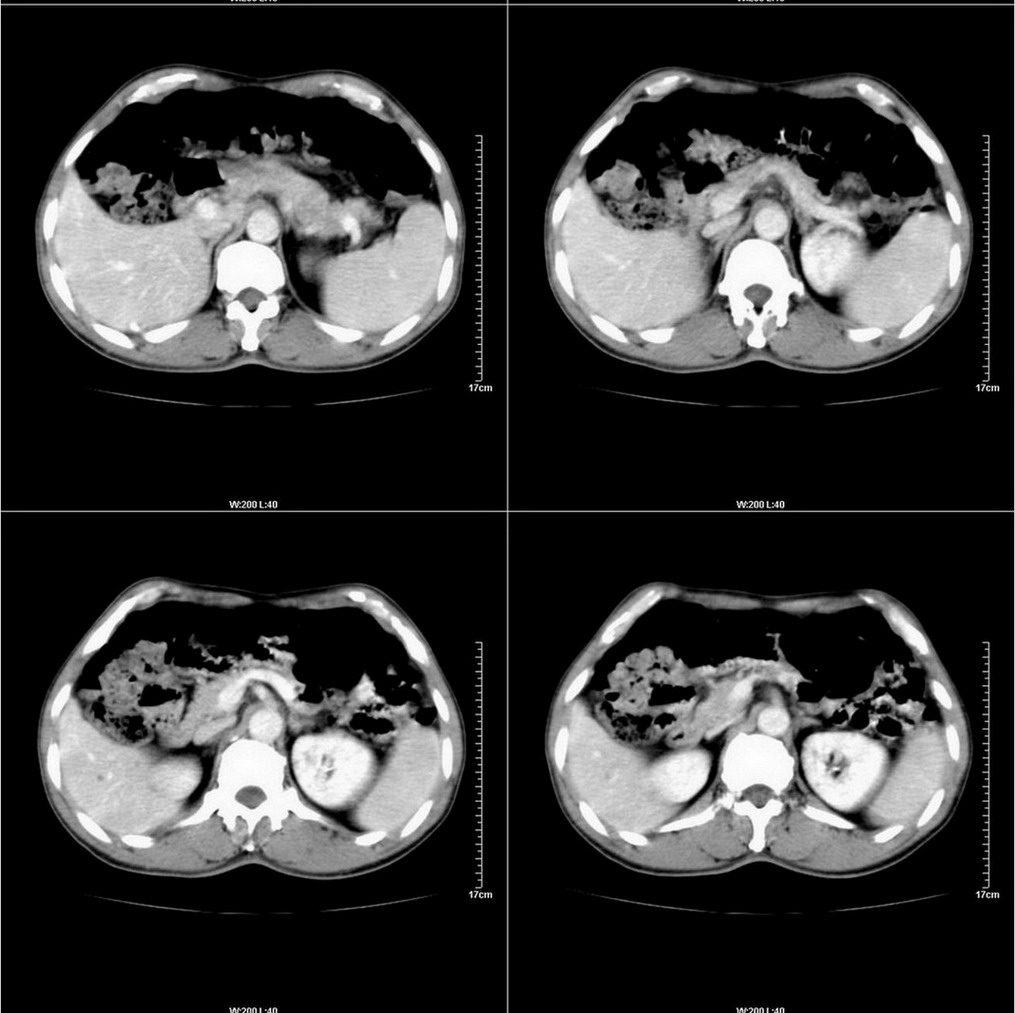

标题: CT14220:男性,59岁。腹部疼痛不适半年余。 [打印本页]

标题: CT14220:男性,59岁。腹部疼痛不适半年余。

胃壁弥漫增后,考虑胃炎溃疡

建议结合胃镜或钡餐检查,考虑胃底贲门癌可能性大。

考虑:1、肝右叶下部小囊肿;

2、胃可能为准备充盈不良所致,必要时请胃镜进一步检查。